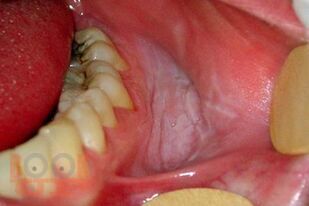

Методические рекомендации разработаны на основании законодательных и научных литературных данных. В рекомендациях изложены общие сведения об онкологических заболеваниях челюстно-лицевой области, алгоритмы и способы диагностики, профилактики злокачественных новообразований, особенности их клиники при различных локализациях на лице и в полости рта. Представлена тактика врача при подозрении на онкозаболевание, указаны предраковые состояния, которые требуют особого внимания специалистов. Методические рекомендации предназначены для организаторов здравоохранения, врачей первичного звена, врачей специалистов, студентов стоматологических факультетов, интернов, врачей-ординаторов.